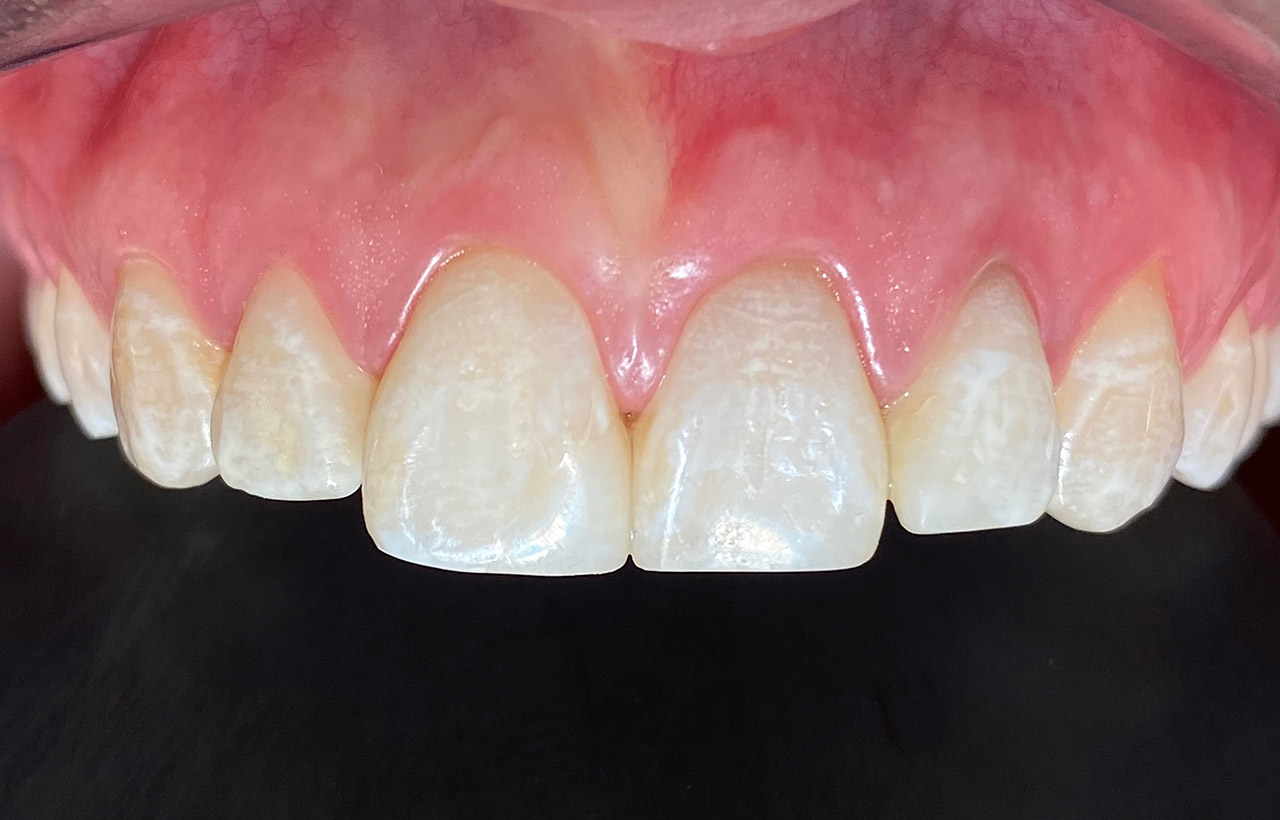

Internes und Externes Bleaching (Bleichen):

Nach Unfall mit E-Scooter unbefriedigendes Ergebnis der Erstversorgung (alio loco). Therapievorschlag: Stiftzähne?

Unsere minimalinvasive Therapie: Revision der Wurzelbehandlungen, danach internes und externes Bleaching, adhäsive Kunststoffüllungen in Schichttechnik. (Titel meiner Diplomarbeit 2003 “Die Vermeidung von Extraktion und Wurzelspitzenresektion durch zeitgemässe Endodontie in der Privatpraxis”)